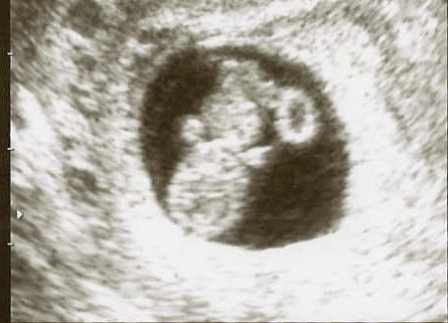

Baby Leo :lol: :lol: :lol: :lol:

Tökéletes bébi (ezt tudtam eddig is :wink: )

MrsLeo: Nagyon jó! Már egészen emberformája van! :D Azért te sem bírtad ki a 12. hétig :wink: Hátha én is ilyen klassz képet kapok szerdán :roll: :roll: :roll: :lol:

De jó kis képed van!!!! Én is voltam pont 8+0 napon, de nem adtak képet... :(